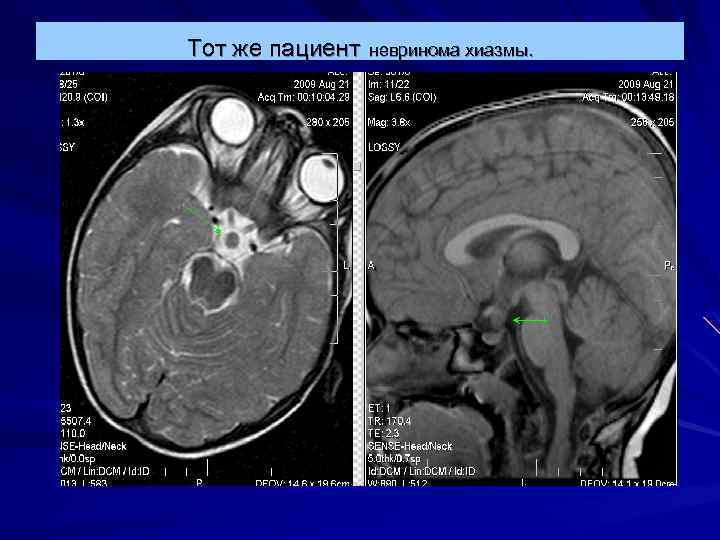

Тот же пациент невринома хиазмы.